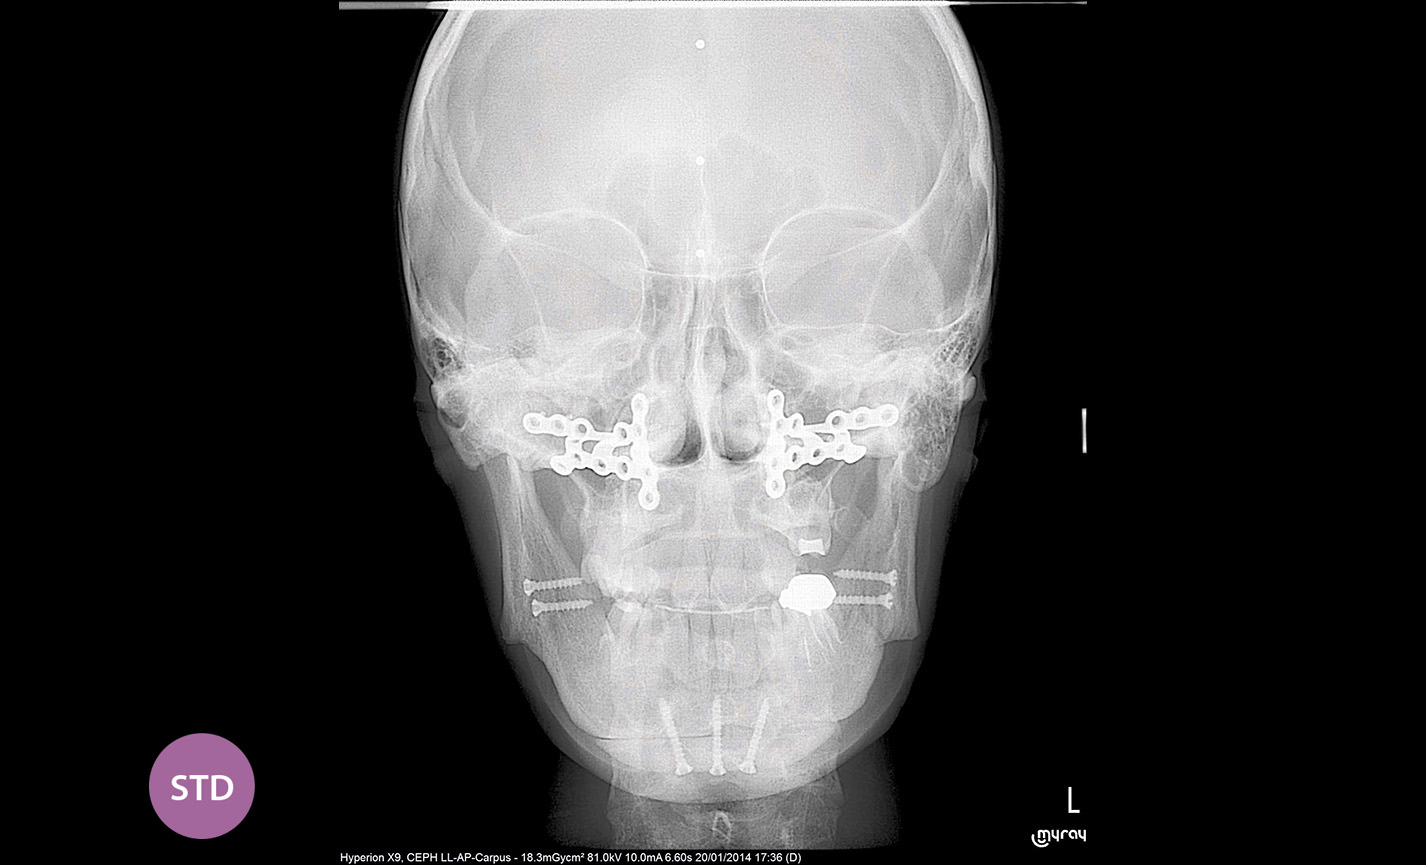

Téléradiographie

Antéro-postérieure : pour investiguer les asymétries et les malocclusions en vue d’un traitement correct.

Applications orthodontiques

Des FOV de 10 cm de diamètre sont nécessaires pour l’étude des troisièmes molaires incluses car, chez un adulte de taille moyenne, la distance entre les troisièmes molaires de droite et de gauche, en incluant leurs racines respectives, le processus alvéolaire et l’os avoisinant, est d’au moins 9 cm. Les champs de vision réduits sont utiles en cas d’analyse de dents incluses ou surnuméraires, pour limiter la dose à la seule région d’intérêt. En effet, pour une planification correcte du traitement, il est fondamental de déterminer la position réelle (vestibulaire ou palatine), possible uniquement avec une analyse 3D, même à très faible dose avec un protocole QuickScan. Le champ de vision complet 13 x 16 cm permet une évaluation minutieuse des voies aériennes supérieures, souvent utile pour compléter une investigation en vue d’un traitement orthodontique qui tienne compte des problématiques oto-rhino-laryngologiques.